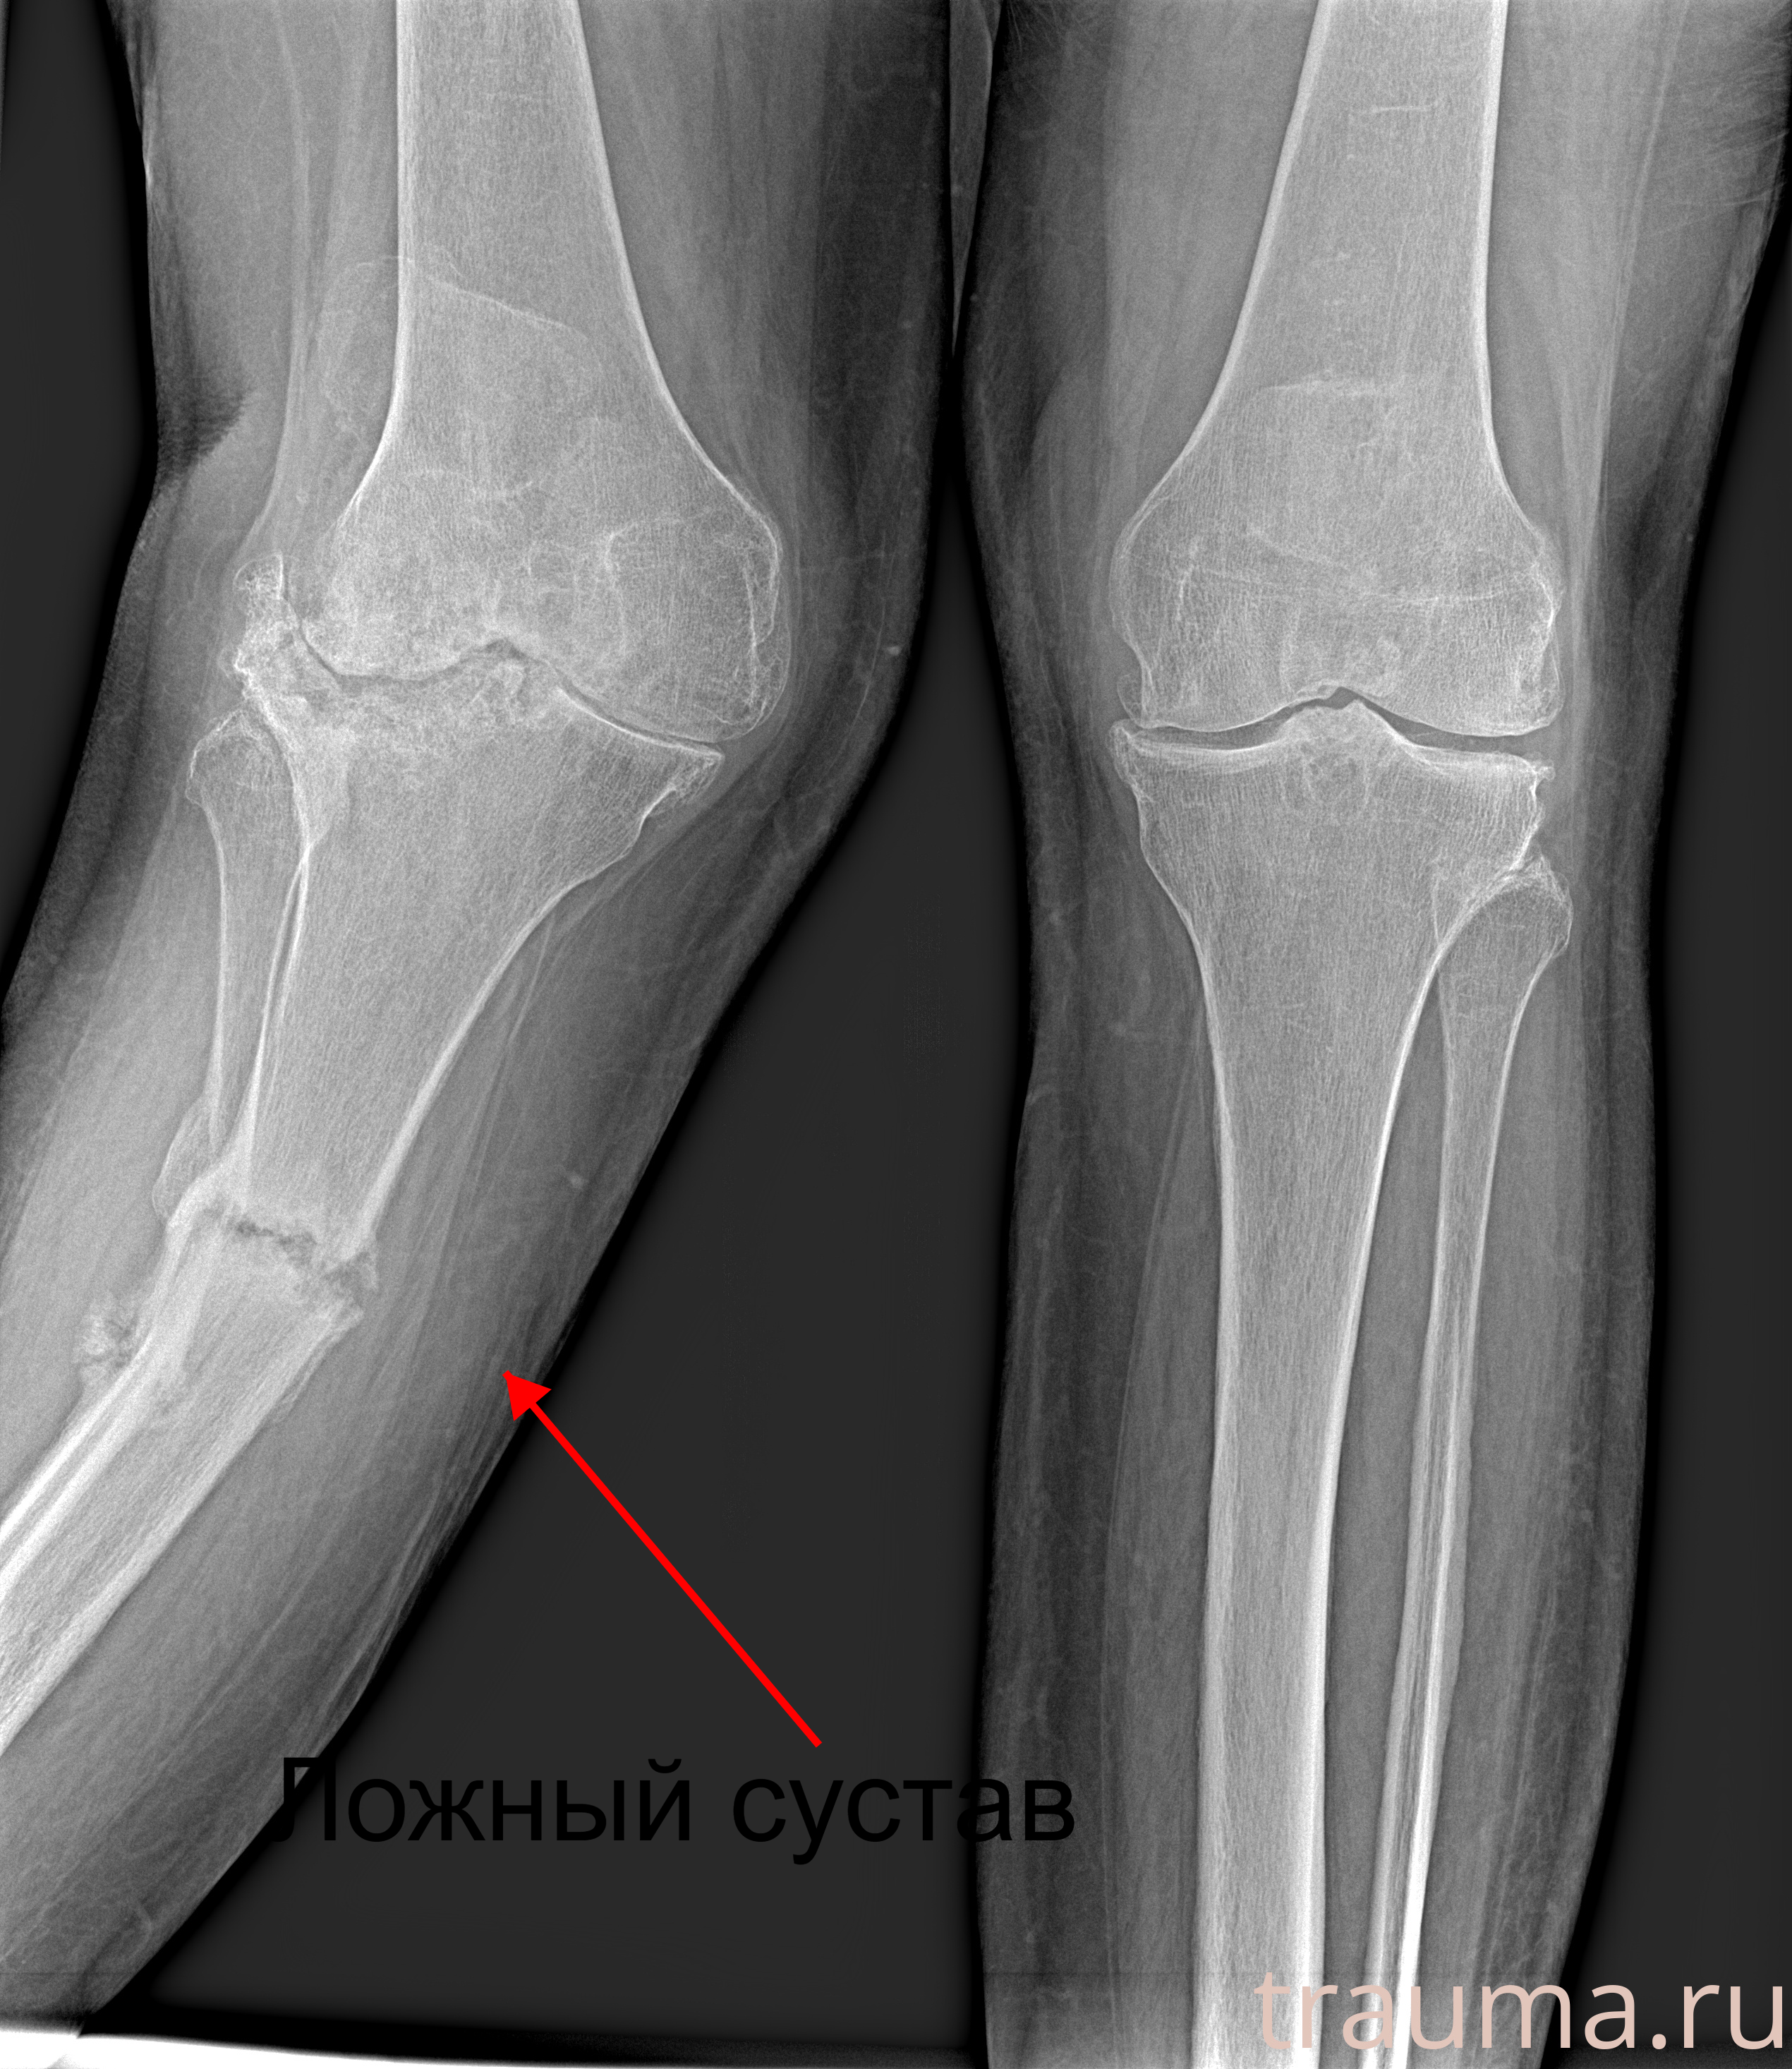

Рентгенограммы